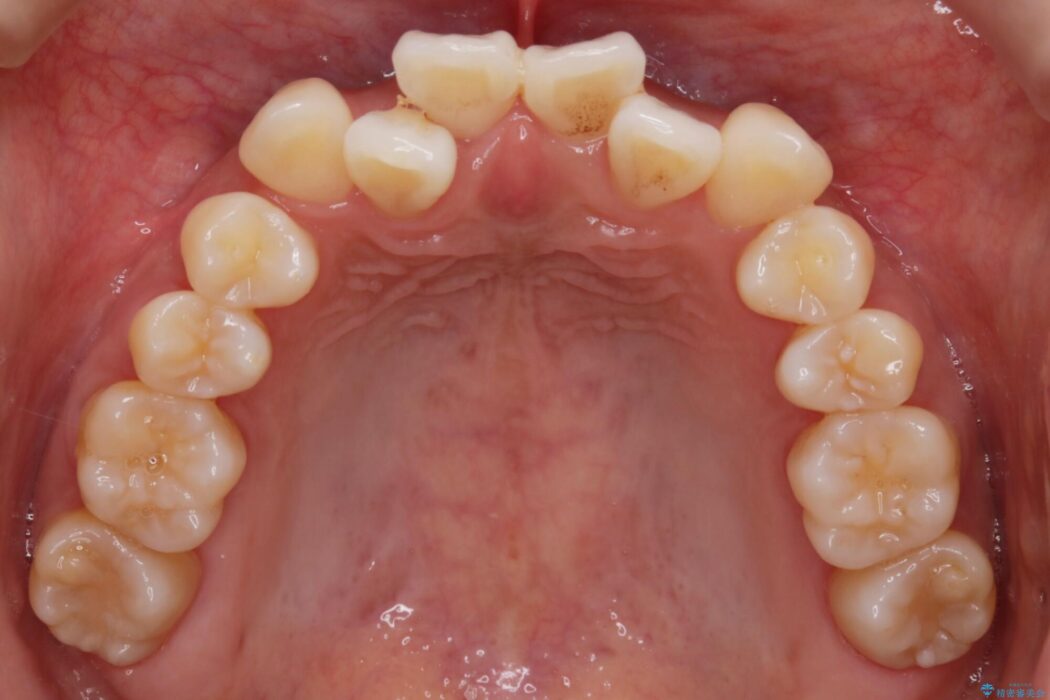

前歯のガタガタを気にされて来院されました。

検査の結果、骨の厚みに余裕がないことが判明しましたので、幅の拡大と歯の側面を削るIPRでは歯周病に対する不安を拭いきれないと判断しました。

よってマイクロインプラントを用い、奥歯から順番に遠心移動させることによってスペースを確保することにしました。